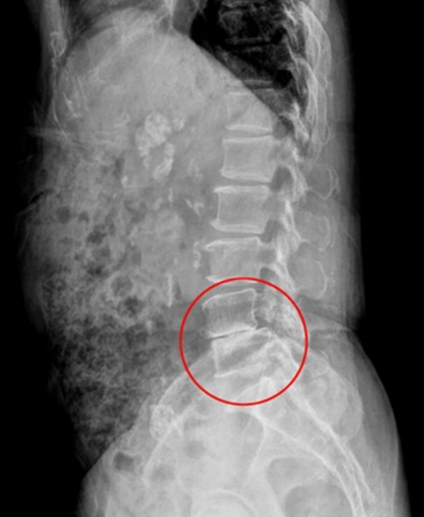

최소침습 척추고정술

척추고정술은 척추의 이상 정렬을 수정하고 고정하는 수술방법

이며 척추의 안정성을 회복시키고 통증을 완하하는데 도움을 줍니다.

주로 뼈의 고정이 필요한 경우 진행되며, 문제가 되는 병변 부위를 제거한 후 척추를 고정시킵니다. 디스크와 협착증의 재발 가능성을 차단하여 수술 후 만족도가 매우 높습니다

최소침습척추고정술 (수술전)

최소침습척추고정술 (수술후)